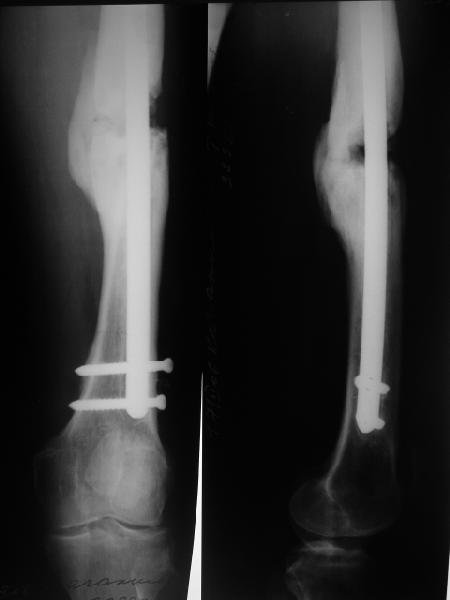

Рефрактур уж точно можно будет не опасаться, а за несколько месяцев даже при отсутствии заполнения костью по всей окружности, этот обходной "мостик" упрочнится и возьмет на себя нагрузку. В приложении пример такого рода "эндопротезирования диафиза", прошло больше 3 лет.

Пациентка, страдающая еще и инсулинозависимым диабетом, не хромает, работает инженером.